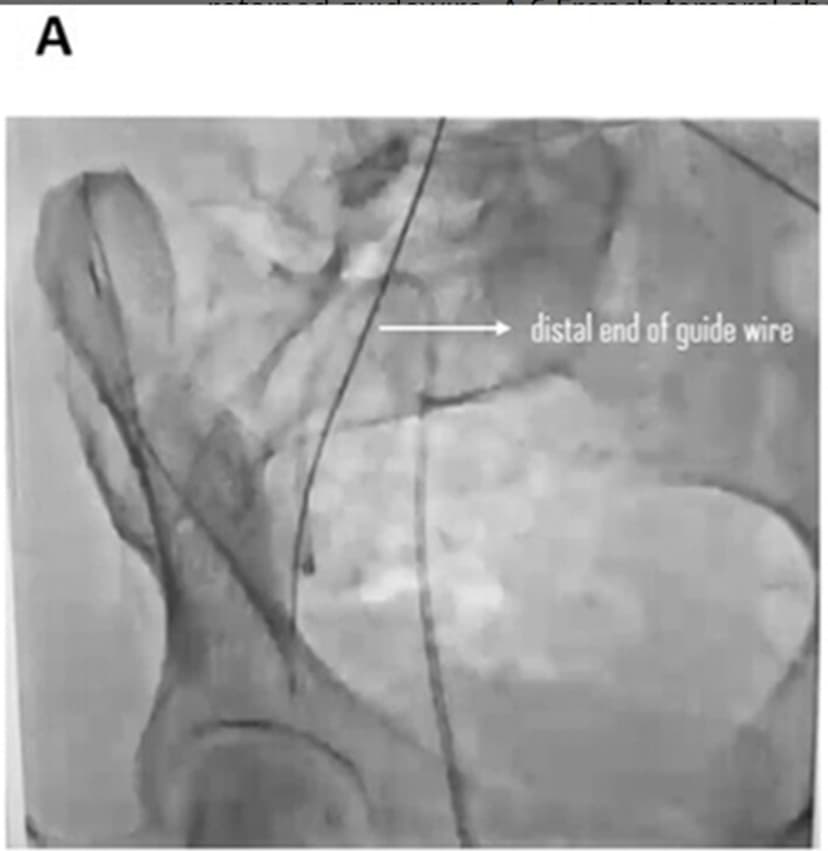

A routine medical procedure has led to a startling discovery in Afghanistan, where a 50cm medical wire was left inside a 45-year-old woman for three months. The patient, who has a long history of uncontrolled high blood pressure and end-stage kidney disease, was undergoing regular hemodialysis when an X-ray revealed the unexpected finding. The wire, a guidewire used to assist in placing a catheter, had been mistakenly left behind during a prior procedure at another hospital.

Following the discovery, the guidewire was surgically removed with the patient's consent. Subsequent scans confirmed the successful removal, and the patient was discharged in stable condition. This case serves as a critical reminder of the inherent risks in medical procedures and the ongoing need for enhanced safety measures to protect patients, particularly those undergoing long-term treatments like dialysis.